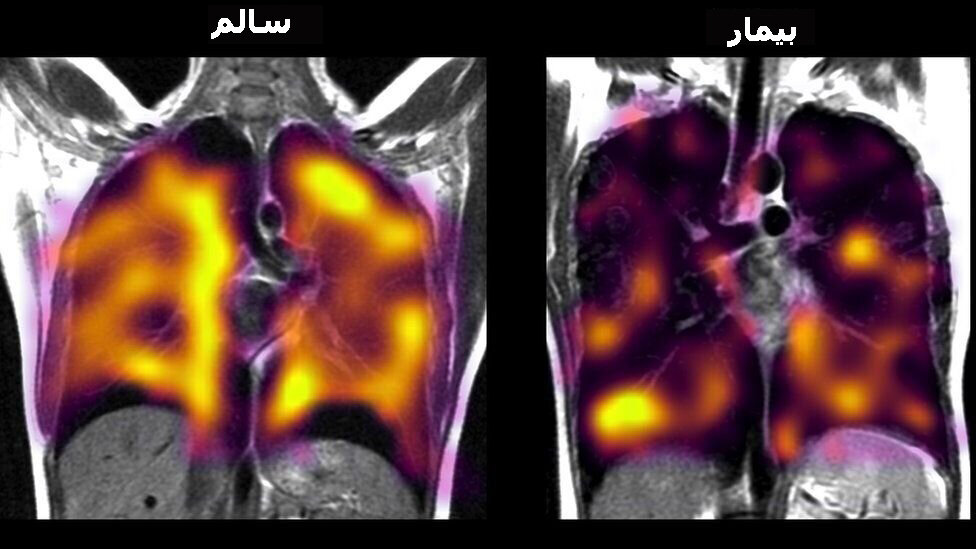

به گزارش همشهری آنلاین به نقل از بیبیسی دانشمندان در این بیماران از یک روش جدید اسکن گاز زنون برای شناسایی ناهنجاریهای ریوی استفاده کردند که اسکنهای معمول آنها را نشان نمیدهند.

این پژوهشگران اسکنهای گاز زنون و سایر آزمایشهای کارکرد ریه را در سه گروه افراد مقایسه کردند.

همه این افراد در حین انجام امآرآی (تصویربرداری تشدید مغناطیسی) گاز زنون استنشاق کردند.

این گاز بسیار شبیه به اکسیژن عمل میکند، اما میتوان در جریان انجام اسکن به صورت تصویری آن را دنبال کرد، بنابراین دانشمندان میتوانستند «ببینند» میزان جذب این گاز از ریهها به درون جریان خون - که گام مهمی در انتقال اکسیژن به بدن شمرده میشود- چقدر است.

یافتههای این پژوهشگران نشان داد در اکثریت افراد مبتلا به کووید درازمدت، انتقال گاز نسبت به افراد گروه کنترل که سالم بودند، با کارآمدی کمتری انجام میشود.

در اغلب موارد رادیوگرافیهای اشعه ایکس و سیتی اسکنهای معمول ناهنجاریهایی هیچ ناهنجاری را در افراد مبتلا به کووید درازمدت نشان نمیدهند.